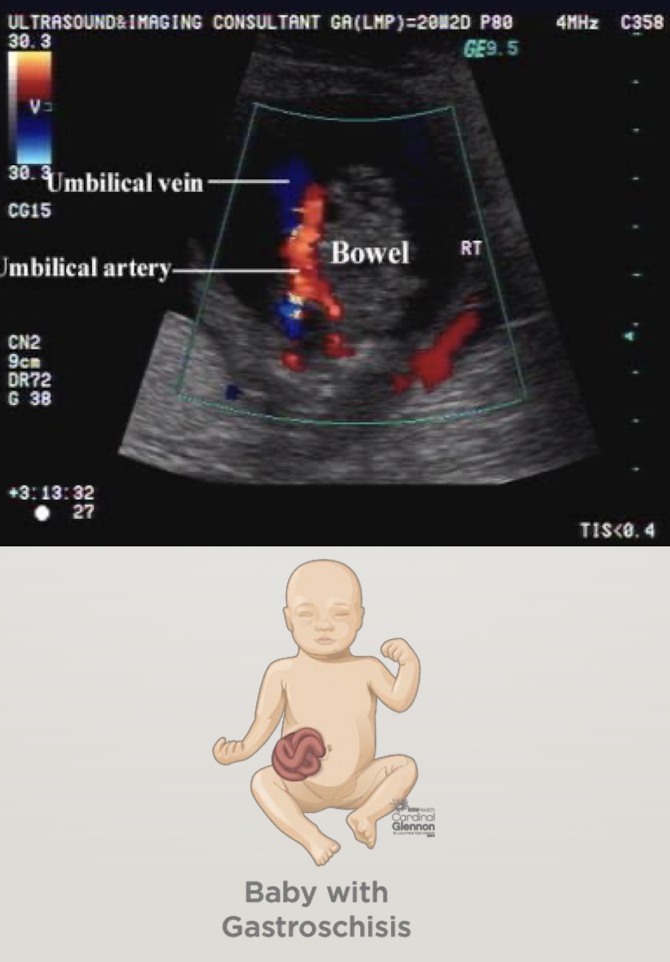

abdominal cord insertion (ACI)

becomes belly button after born

umbilical cord seen entering fetal abdomen just above level of bladder

UV courses to liver within falciform ligament

UAs course on either side of bladder

2VC can cause IUGR or is an indication of chromosomal abnormality

SONO:

image ACI with and without color Doppler

ensure smooth abdominal cord insertion (should be nothing “pooching” out)

rule out gastroschisis and omphalocele

gastroschisis

“loose bowel pooching out—floating outside abdomen”

omphalocele

bowl or other organs come out, BUT difference is… it will be encased in a membrane

looks like a contained mass with smooth borders b/c of membrane